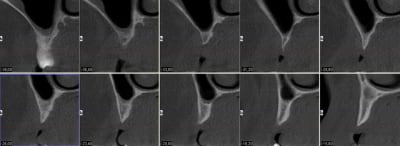

sur ton analyse quel est le diamètre de l'implant 1 en position latéral?

Largeur de la crête me semble être au dessus de 5mm... Greffe ROG standart,non? pourquoi un bloc?

a bien regarder, diamètre de l'implant 4mm et crête environ la même chose... un peu trop large comme implant pour le site, non?

diamètre 3.7mm pour les 2 implants

je vérifierai lundi (j'ai pas l'analyse à la maison) mais il me semble que le site de la 53 est encore pire que pour la 12...

sincèrement, pour la 12 j'ai longtemps hésité entre expansion/greffe...maintenant, vu qu'il faut de toutes façon greffer en 23...